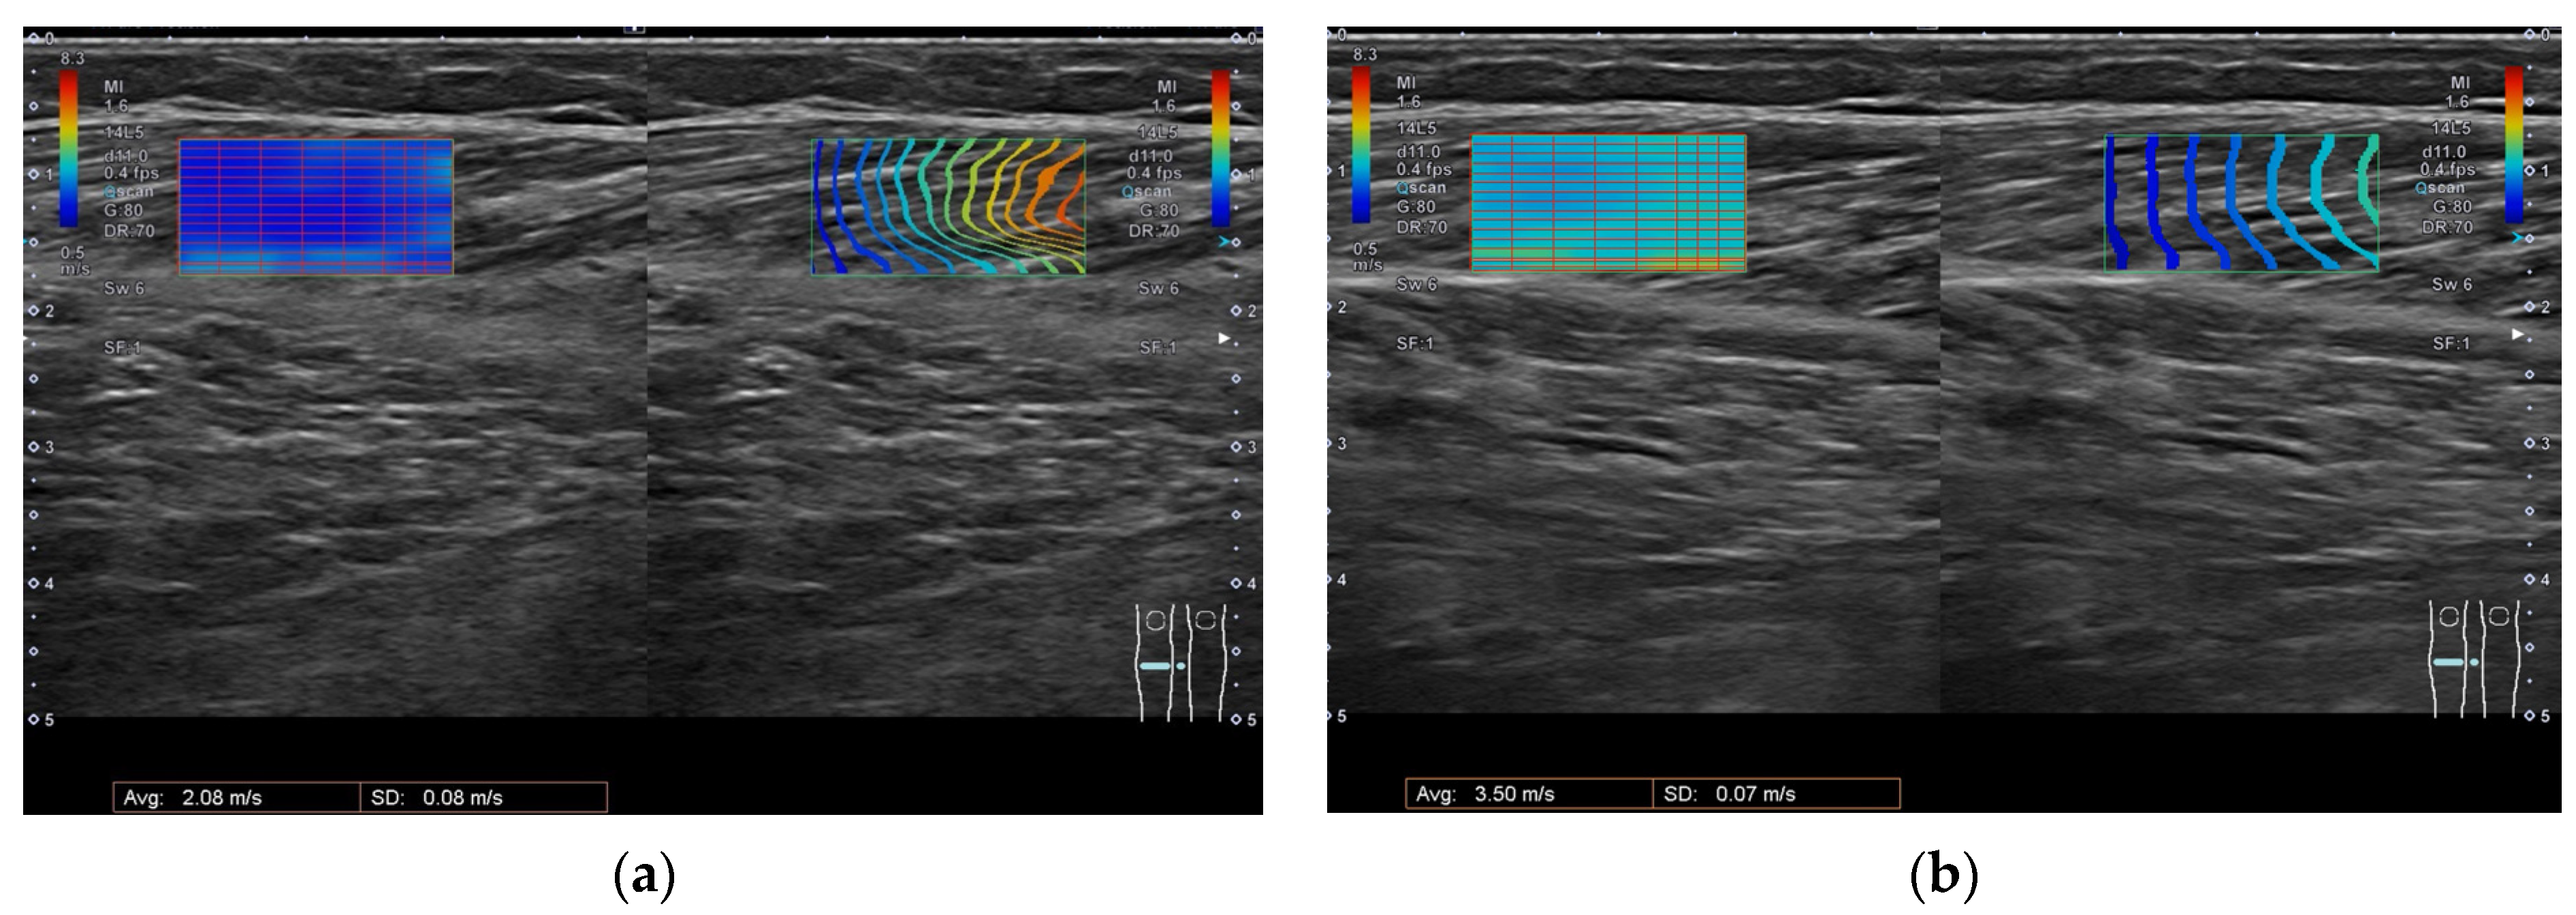

| after | 1.5 | 1.5 | −10 | 0 | 2.08 | 3.5 | |||||||||

| 9 | before | 59 | M | L | H | 12.9 | 20/0/40 | 29 | 4 | 3 | 2 | −30 | −10 | 2.76 | 6.78 |

| SWV at rest (m/s) (Median (IQR)) | 2.52 (2.21–2.67) | 2.24 (2.00–2.42) | 0.093 |

| SWV stretched (m/s) (Median (IQR)) | 4.00 (3.47–6.77) | 2.98 (2.74–3.52) | * 0.005 |